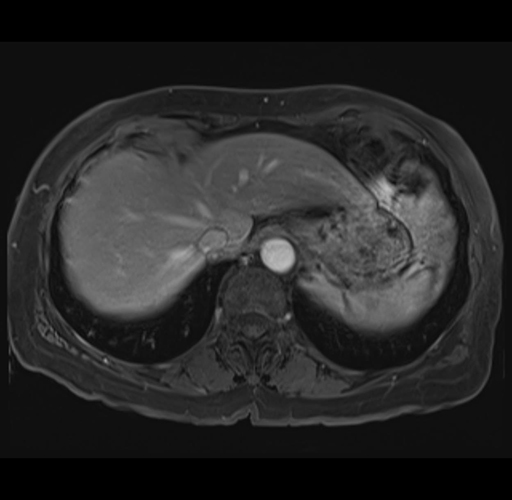

MRI T1